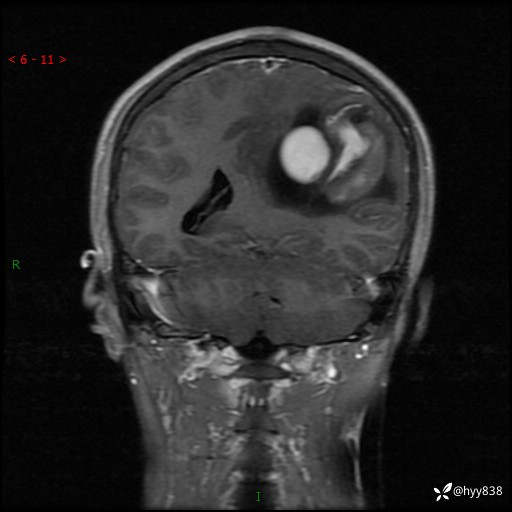

病例年轻小伙,头痛伴呕吐半年,渐进性加重1月。疑难病例,第一次见--结果公布~

性别:男

年龄:21岁

简要病史:头痛伴呕吐半年,渐进性加重1月

颅脑MRI平扫+增强